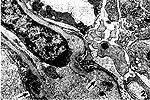

1.3 超微病理 肾活检组织常规电镜包埋,超薄切片经醋酸铀、枸橼酸铅双重染色,HU-12A型电镜下观察摄片。对肾小球7种主要超微结构病变,即系膜旁区半球形沉着(图1)、内皮下及上皮下沉着(图2)、系膜溶解(图3)、旁区病变(图4)、基膜异常(包括基膜变薄和基膜溶解(图5)、系膜细胞插入(图6)的程度和累及范围,均用半定量方法分为0~Ⅲ级。

图1 肾小球系膜旁区见大量沉着物,有的呈半球状. ×3000 图2 基膜上皮下致密沉着物,伴部分溶解吸收. ×6000 图3 系膜区基质密度明显降低,甚至溶解消失. ×4000 图4 系膜旁区上皮下水肿,足突脱落或裂隙增宽. ×6000 图5 基膜密度明显降低,致密层溶解变薄甚至断裂. ×7000 图6 系膜细胞向基膜内伸入,致基膜明显增厚. ×4800